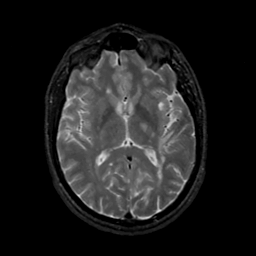

MR Study #17, July 7, 1991 -- Slice #26